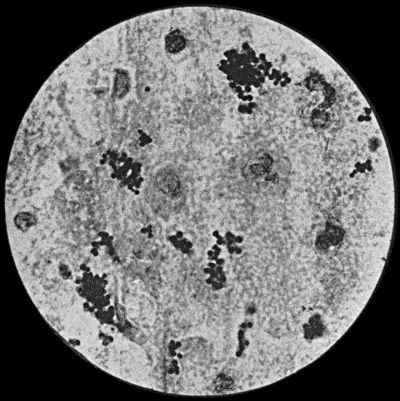

15 2.Staphylococcus aureus in Pus from case of Osteomyelitis

Fig. 2.—Staphylococcus aureus in Pus from case of Osteomyelitis. × 1000 diam. Gram's stain.

Staphylococcus Aureus.—This is the commonest organism found in localised inflammatory and suppurative conditions. It varies greatly in its virulence, and is found in such widely different conditions as skin pustules, boils, carbuncles, and some acute inflammations of bone. As seen by the microscope it occurs in grape-like clusters, fission of the individual cells taking place irregularly (Fig. 2). When grown in artificial media, the colonies assume an orange-yellow colour—hence the name aureus. It is of high vitality and resists more prolonged exposure to high temperatures than most non-sporing bacteria. It is capable of lying latent in the tissues for long periods, for example, in the marrow of long bones, and of again becoming active and causing a fresh outbreak of suppuration. This organism is widely distributed: it is found on the skin, in the mouth, and in other situations in the body, and as it is present in the dust of the air and on all objects upon which dust has settled, it is a continual source of infection unless means are taken to exclude it from wounds.